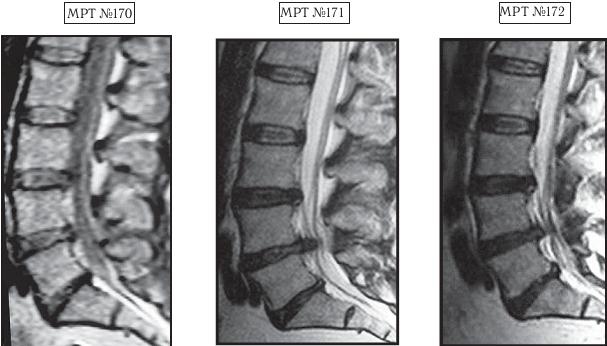

На МРТ № 170 наблюдается состояние поясничного отдела позвоночника: ретроспондилолистез LV (соскальзывание позвонка относительно другого позвонка), протрузии межпозвонковых дисков в сегментах LII—LIV и LIV-LV

На МРТ № 171 наблюдается состояние поясничного отдела позвоночника: ретроспондилолистез LV увеличение протрузии межпозвонкового диска в сегменте LIII-LIV, образование секвестрированной грыжи межпозвонкового диска в сегменте LIV-LV с разрывом задней продольной связки, абсолютный стеноз на этом уровне.

На МРТ № 172 — состояние поясничного отдела позвоночника в середине первого курса лечения методом вертеброревитологии (после двух недель от начала лечения): наблюдается положительная динамика, выраженная ретрузия секвестра грыжи межпозвонкового диска в сегменте LIV-LV, визуально прослеживается увеличение высоты межпозвонкового диска в том же сегменте, что свидетельствует о начавшемся активном процессе его восстановления, значительное уменьшение стеноза спинномозгового канала на данном уровне.